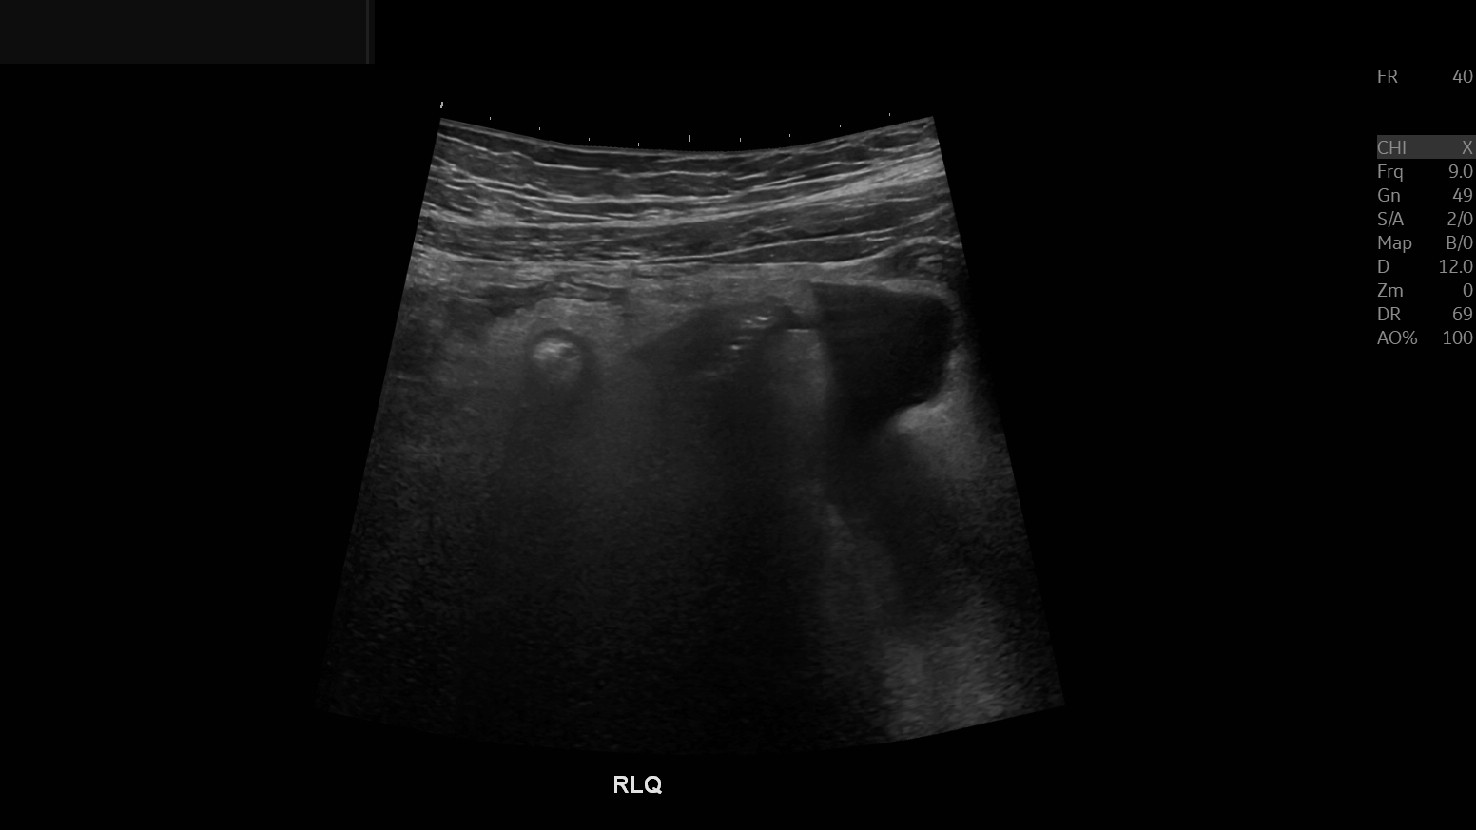

Appendicitis 12

0.9 cm positive appendicitis, with peripheral free fluid, and fat stranding.